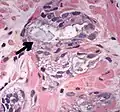

• Collagenous micronodules[4]

• Glomerulations,[4] epithelial proliferations into one or more gland lumina, typically a cribriform tuft with a single attachment to the gland wall.[18]

• Perineural invasion.[4] It should be circumferential[18][notes 5]

• Angiolymphatic invasion[4]

• Extraprostatic extension [4]